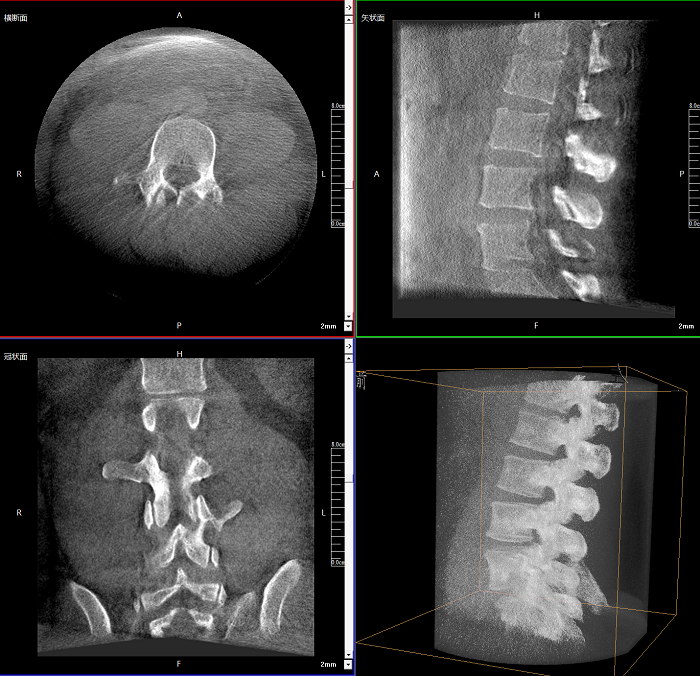

三維成像 全面觀察

任意視角、任意切面觀察

術(shù)中實(shí)時(shí)生成橫斷面、矢狀面、冠狀面及三維影像,可在任意切面、任意角度評(píng)估植入物和解剖結(jié)構(gòu)的相對(duì)位置。

術(shù)中CT檢查 減少翻修概率

通過(guò)術(shù)中三維影像的檢查,可以立即發(fā)現(xiàn)植入物的錯(cuò)位,減少不必要的第二次手術(shù),減少并發(fā)癥概率以及感染風(fēng)險(xiǎn)。